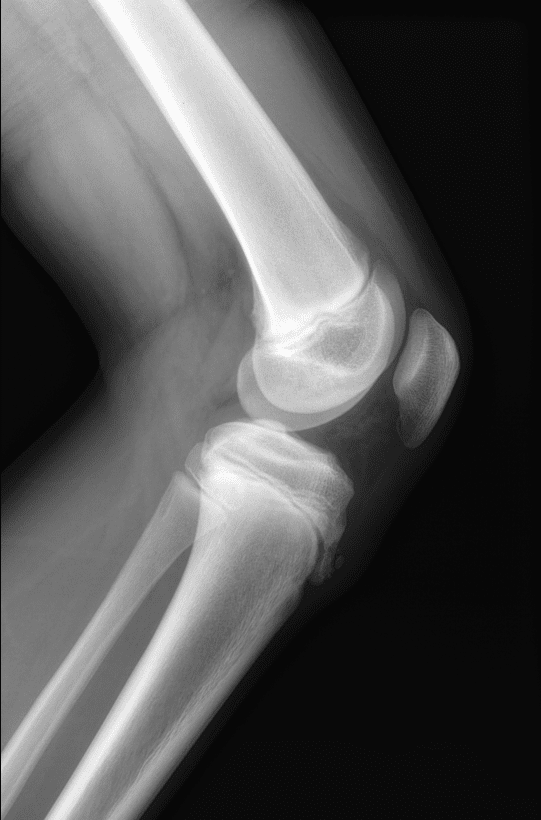

Viêm lồi củ trước xương chày

Viêm lồi củ trước xương chày - Ảnh 2

» Thông tin: Nam giới – 10 tuổi.

» Lâm sàng: Sưng đau đầu trên xương chày.